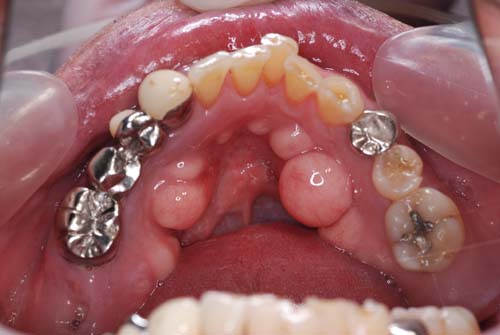

| 今回の写真は下顎隆起です。下顎骨の内側が写真の様に出っ張っています。症状はありません。これは、歯でも根でも無く骨なのです。腫瘍ではないかと心配して相談に来る方もいらっしゃいます。しかしただの骨の出っ張りで腫瘍などの悪い病気ではありません。原因は不明ですが小さい物を含めると結構な頻度で出現します。下顎の場合はこの場所で、上顎の場合は真ん中(口蓋中央部)に多いです。 | ![]() ![]() |

| この骨隆起も大きいです。個数、形がほぼ左右対称に出現するのが不思議です。 | ![]() |